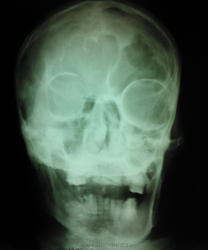

мужчиа 42 года рождения. находится в реанимации с диагнозом ОНМК с правосторонним гемипарезом, повторон. в анамнезе комбинированный митральный порок сердца. Что это такое в височно теменной области слева, энхондрома?  метастаз? на рентгеннограмме ОГК расширен правый корень (центральный рак?) и круглая тень в левом легочном поле (метастаз?). какие будут предположения? в анализах ничего особенного ни СОЭ повышенного ни лейкоцитоза. можно было бы ЛТГ сделать но рентгенаппарат сломался (сгорели инверторы) - так что томки врят ли ожидаются в близжайшее время.

На рентгенокрамме ОГК картина центрального рака правого лёкгого.Наверное,логично предположить метастазирование.

На снимках черепа ничего патологического, особенности строения костей черепа. В легких( на снимке четко видно слово "лЁжа") м. предположить пневмонические, застойные дела, порок сердца, ревматические - или возрастные проблемы. Затемнение в в/д справа - возможна и "инфаркт- пневмония". Корень расширен- скорее, не к онкологии, а к сердечным проблемам.

Верхнее средостение тоже расширено

Перелом 6 ребра слева.

А рядом -МТС...

В ребре метастаз, или в лёгком

То что в костях черепа более вероятно метастазы, менее верятно множественная миелома.. Правый корень расширен, но возможно из-за того что снимали лежа + с/с патология, не похоже что там опухоль

Правое лёгкое пожоже на "раковое",но без бокового не заключу.

+1 попробуйте снять в вертикальном положении с боковым, будет ясно что с легкими

Грудная клетка кардиального больного (скорее всего с поражением клапанов) и  застоем в малом круге/артериальной гипертензией.